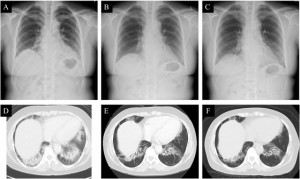

<Abstract:> The incidence of breast cancer in patients with pre-existing interstitial lung disease has been rarely reported. Consequently, evidence supporting the safety of chemotherapy in this population remains limited. This report describes the case of a 55-year-old woman with a history of cryptogenic organizing pneumonia who received adjuvant chemotherapy for the management of breast cancer. The chemotherapy regimen comprised the administration of epirubicin/cyclophosphamide followed by the weekly administration of paclitaxel. This regimen was selected based on the findings of previous studies that assessed the utility of chemotherapy regimens for the treatment of lung cancer in patients with interstitial lung disease. Chemotherapy was completed without worsening of the cryptogenic organizing pneumonia or the appearance of new abnormal lung fields. Therefore, the administration of epirubicin/cyclophosphamide followed by the weekly administration of paclitaxel may be safe in patients with pre-existing interstitial lung disease. This regimen may be a suitable choice for the perioperative management of this population.